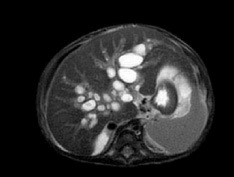

A vascular doppler sonography showed decreased portal venous velocity which indicate portal hypertension. Magnetic resonance cholangiopancreatography (MRCP) disclosed multifocal cystic dilatation of intrahepatic bile ducts, the common bile duct was undetectable appearance suggestive of liver cirrhosis, and splenomegaly (Figure 2).

Figure 2: MRCP.